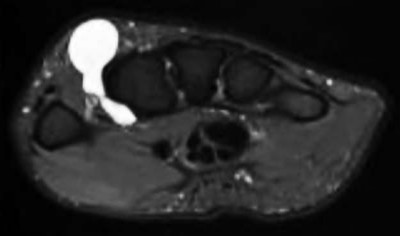

Contrast enhanced MRA of the wrist is typically used to diagnose hypothenar hammer syndrome or other vascular abnormalities.